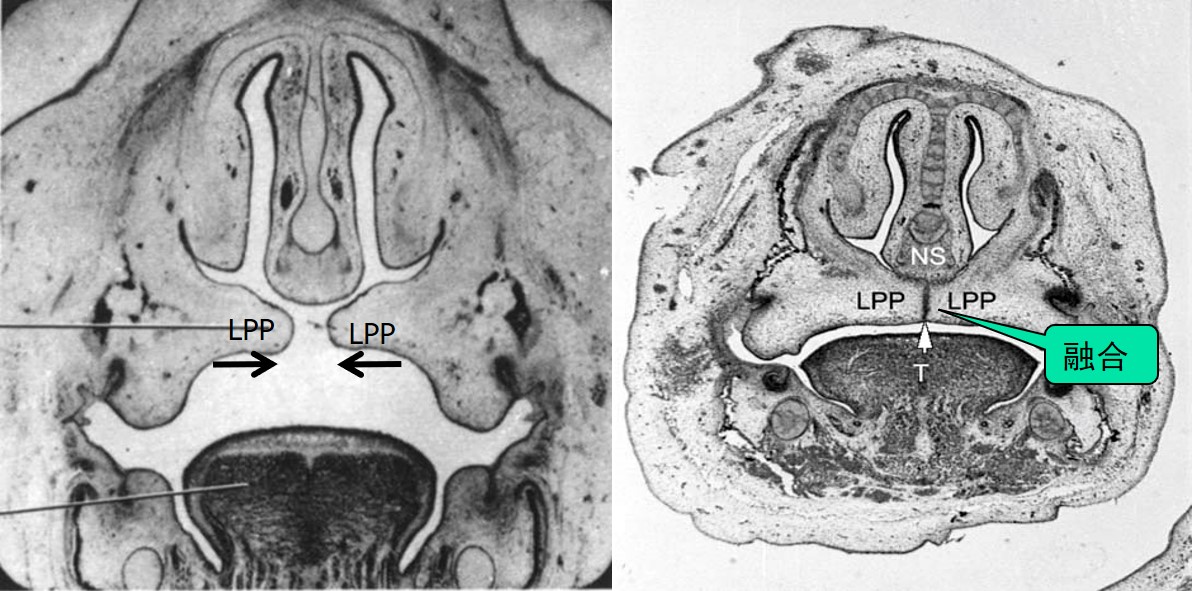

①方向:最初,侧腭突向中线方向生长,由于舌充满了口鼻腔,所以侧腭突向下或垂直方向生长,位于舌的两侧(图1.3-2),胚胎第8周,舌逐渐变扁平,位置下降,侧腭突向水平方向转动并向中线生长(图1.3-3)。

图1.3-3 侧腭突水平方向生长

②两侧侧腭突的运动包括两个过程(图1.3-4):★最初的融合和后来的联合。前腭突和侧腭突联合的中心,留下切牙管,为鼻腭神经的通道,切牙管的口腔侧开口为切牙孔,表面黏膜覆盖为切牙乳头。

图1.3-4 两侧侧腭突的运动